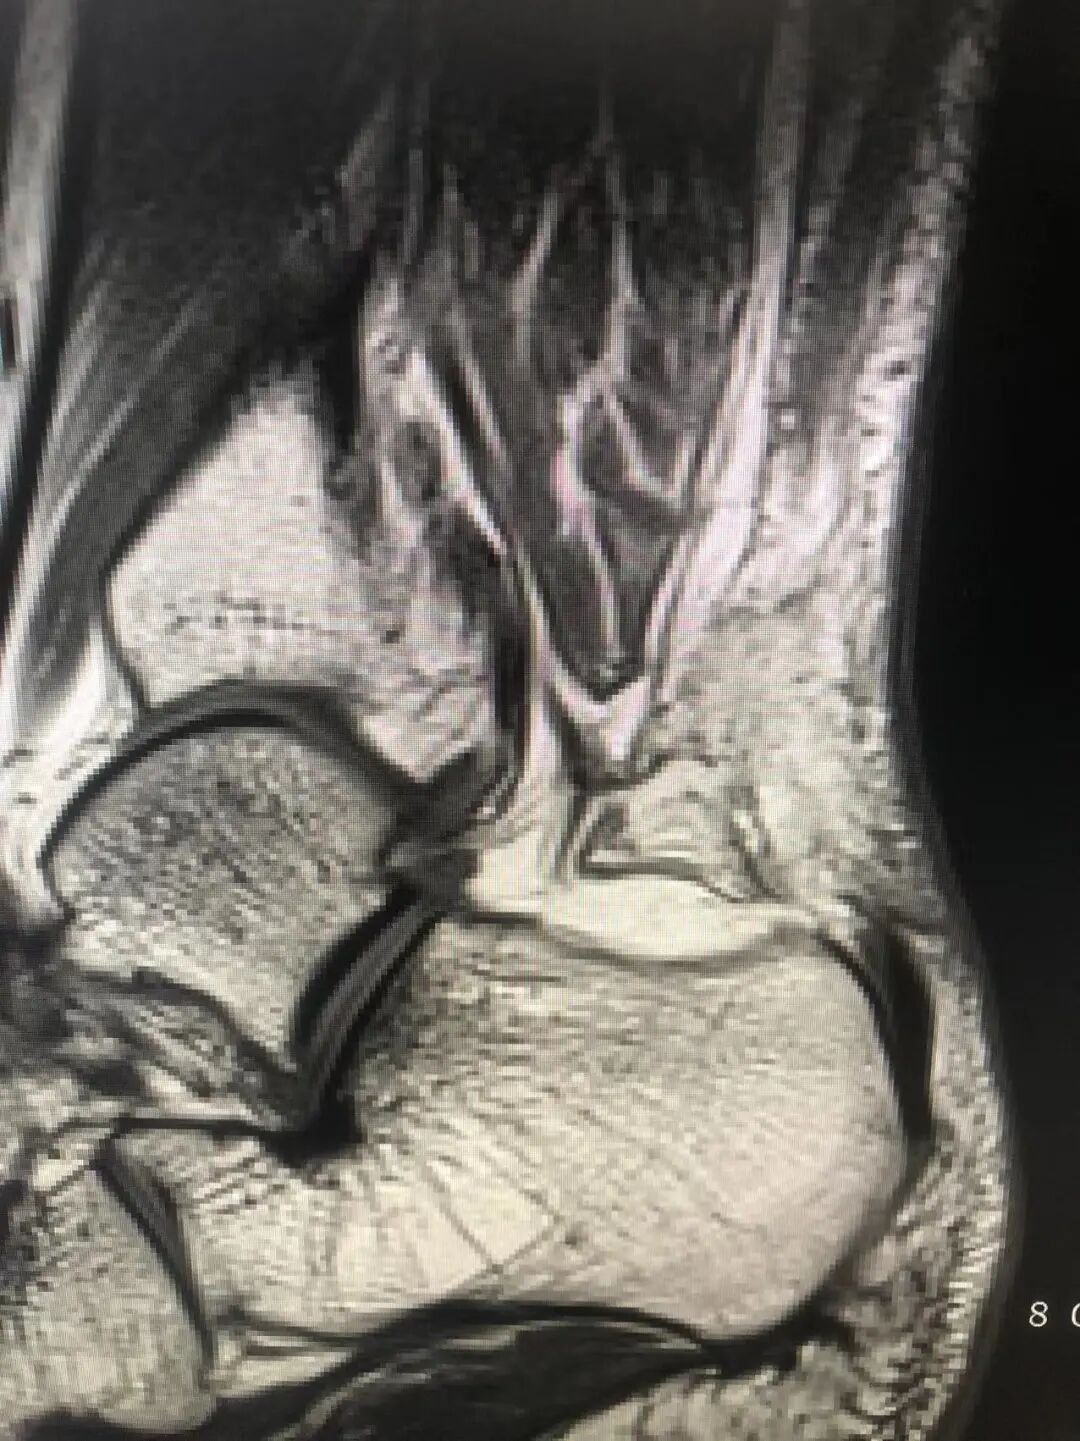

案例2:患者男性,41岁,因“弹跳后出现左足跟肿痛、左踝活动受限6小时”入院,查体:左下肢跛行,左足跟后侧局部肿胀,跟腱处凹陷,压痛,左跟腱区空虚,左踝关节主动背伸活动不能,被动活动好,Thompson征阳性